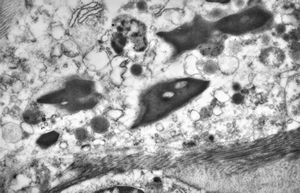

F, 39y. | collagenous and elastin fibers from corium

F, 39y. | collagenous and elastin fibers from corium